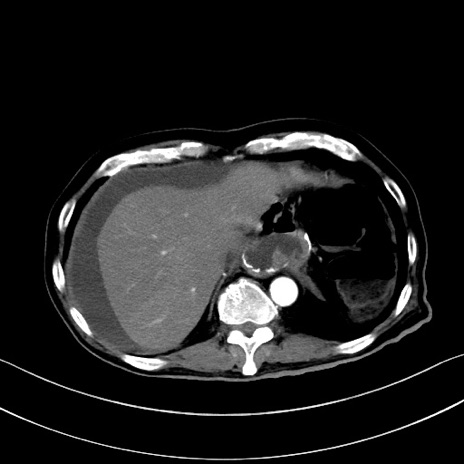

症例28(横断像)

【症例】60歳代男性

【主訴】嘔吐

【現病歴】胃癌にて胃全摘後。食思不振が悪化し、夜中に嘔吐することがある。

【既往歴】胃癌、胃全摘、脾摘、胆摘後

【データ】WBC 5900、CRP 10.56